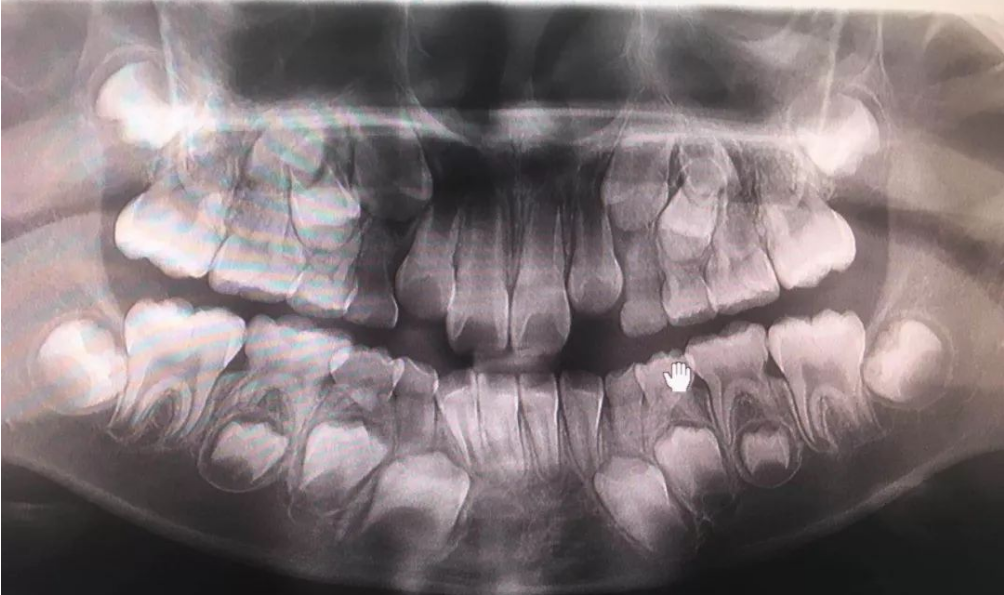

这是非常重要的一个获取空间的方式,可以看到很多牙齿唇倾、牙齿不齐的孩子,从片子上看,她的牙齿都是近中倾斜的,当把牙齿向后直立,每直立10度会获得1.5毫米的空间,如果直立4颗牙那就是6毫米。